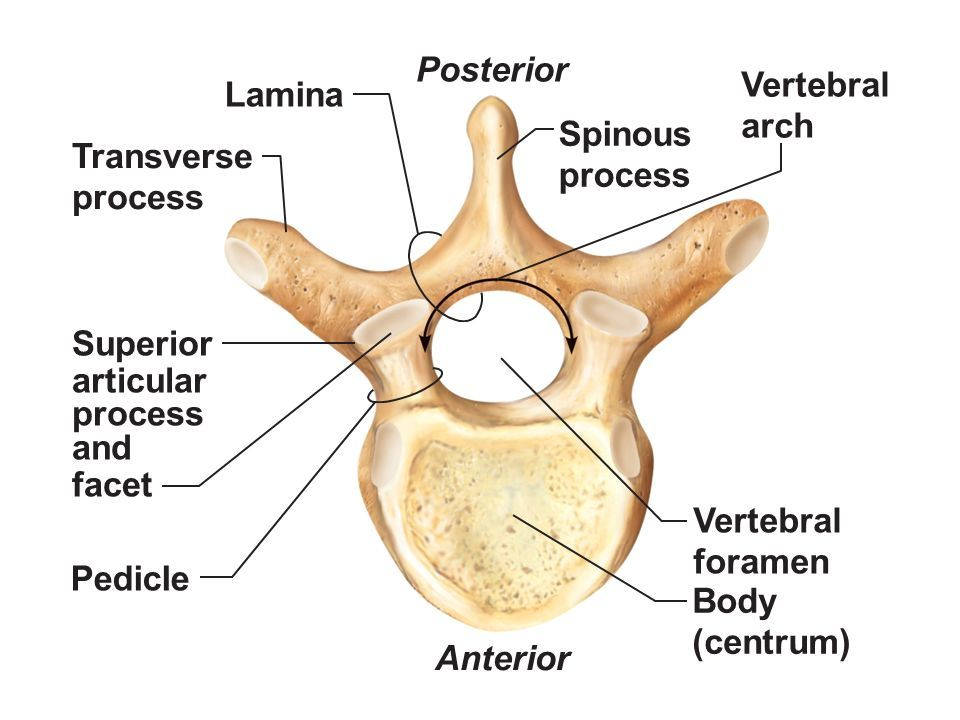

Types of Vertebra

Pedicles

Lamina

Vertebral Foramen